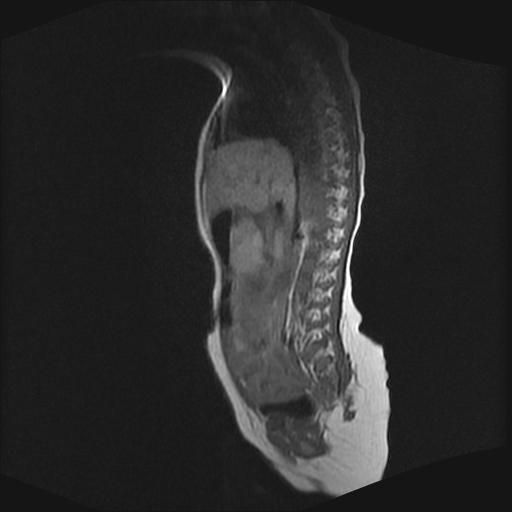

标题: PED0016:脊膜膨出 [打印本页]

标题: PED0016:脊膜膨出

四个月的女婴,ct示脊膜膨出.

脊柱裂、脊膜膨出,请结合临床除外皮毛窦。

脂肪脊髓脊膜膨出

脊柱裂、脊膜膨出